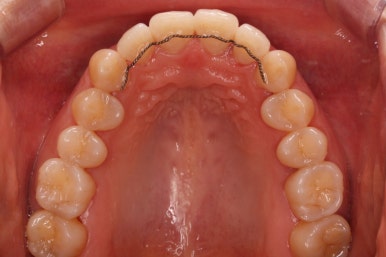

부산설측교정 키다리아저씨치과에서 부분교정을 마무리 하였습니다.

장치를 모두 제거하고 유지철사를 안쪽으로 부착하고 치료를 종료하였습니다.

전후사진을 비교해 보겠습니다.

삐뚤었던 부위들은 가지런하게 정리가 되었습니다.